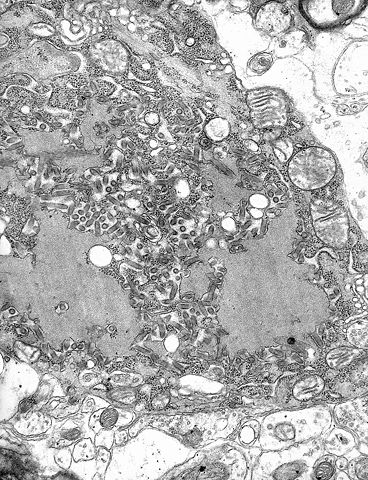

ID#: 1876 Description: Electron micrograph of the Rabies Virus. This electron micrograph shows the rabies virus, as well as Negri bodies, or cellular inclusions.

Content Providers(s): CDC/Dr. Fred Murphy Creation Date: 1975 Copyright Restrictions: None - This image is in the public domain and thus free of any copyright restrictions. As a matter of courtesy we request that the content provider be credited and notified in any public or private usage of this image. |